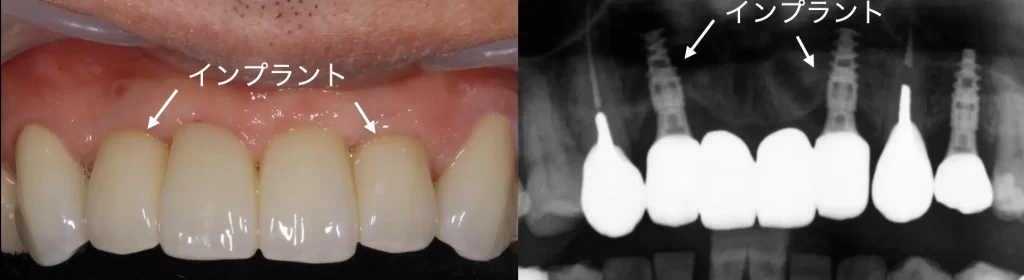

実際に歯根が割れると上の写真のように歯肉が炎症を起こしたり、排膿します。

また、レントゲンでその様子を観察できる場合があります。

インプラント

顎の骨に人工の歯根を埋め込み、歯を作る治療です。

周囲の歯を削らずに治療でき、しっかり噛めるという特徴があります。

西宮北口のアネックスデンタルクリニックでは、インプラント治療の専門医に認定されたDrによる、専門性の高い治療を行っています。